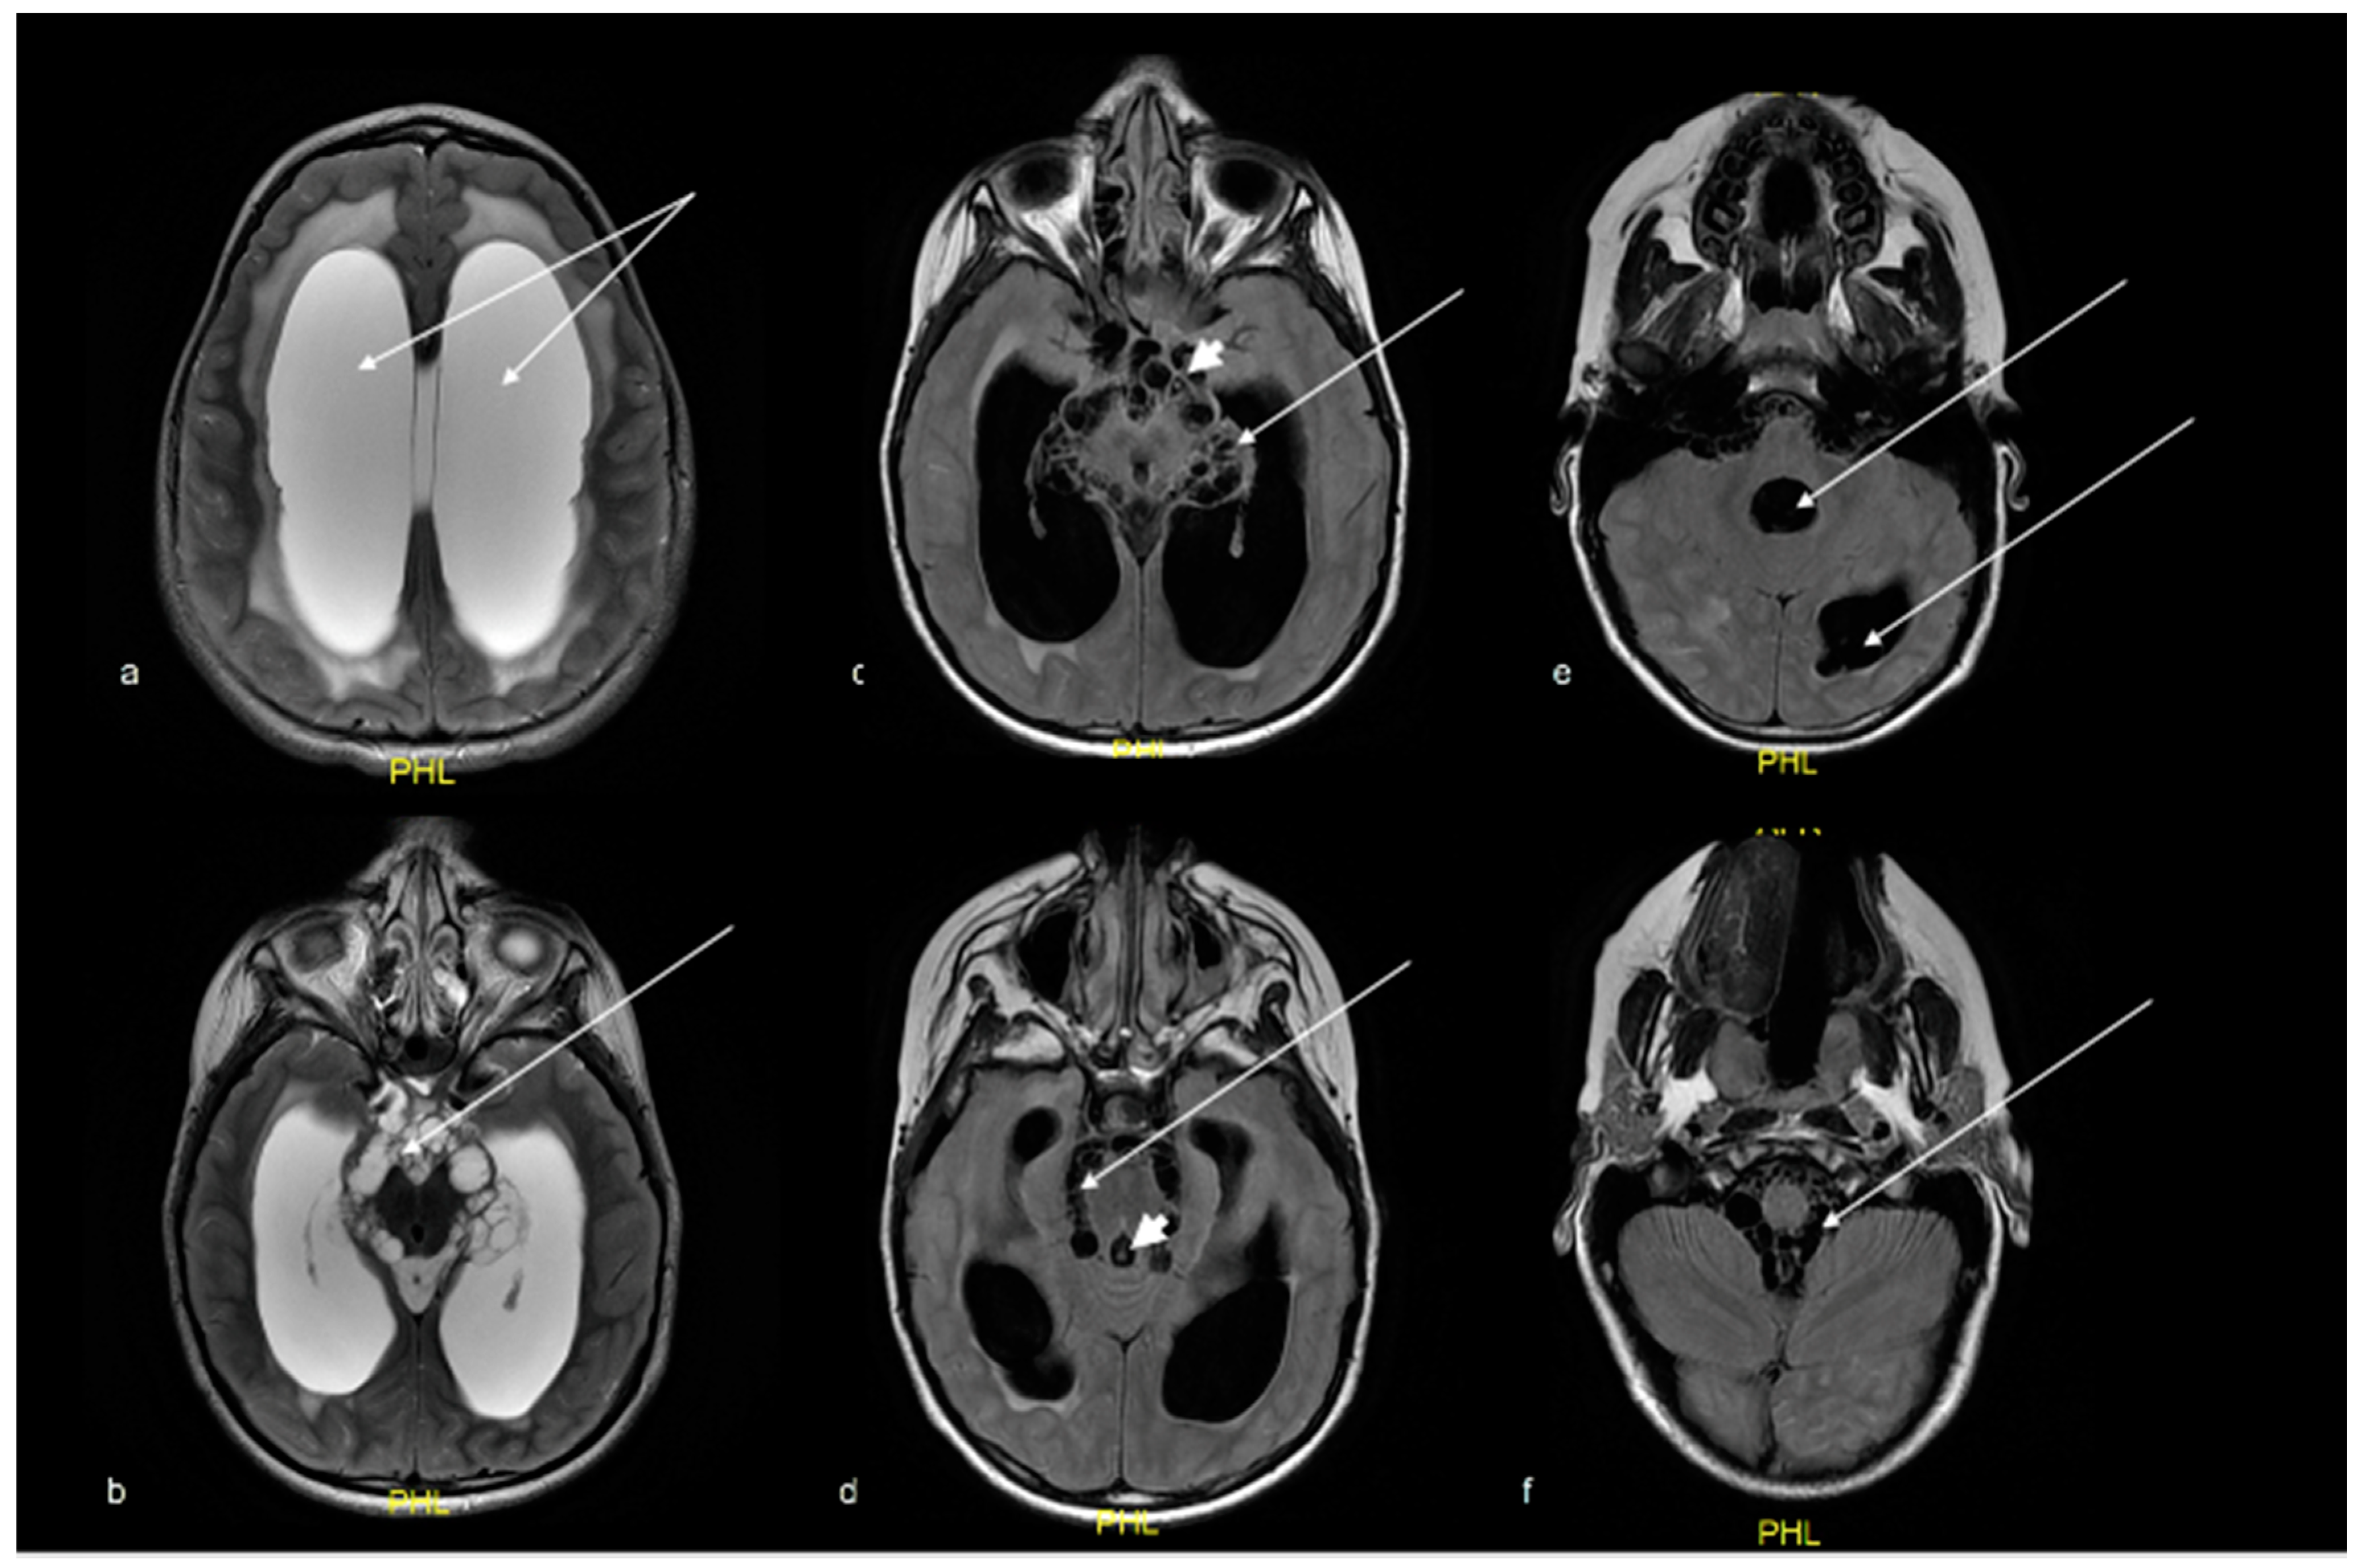

2. Case Report